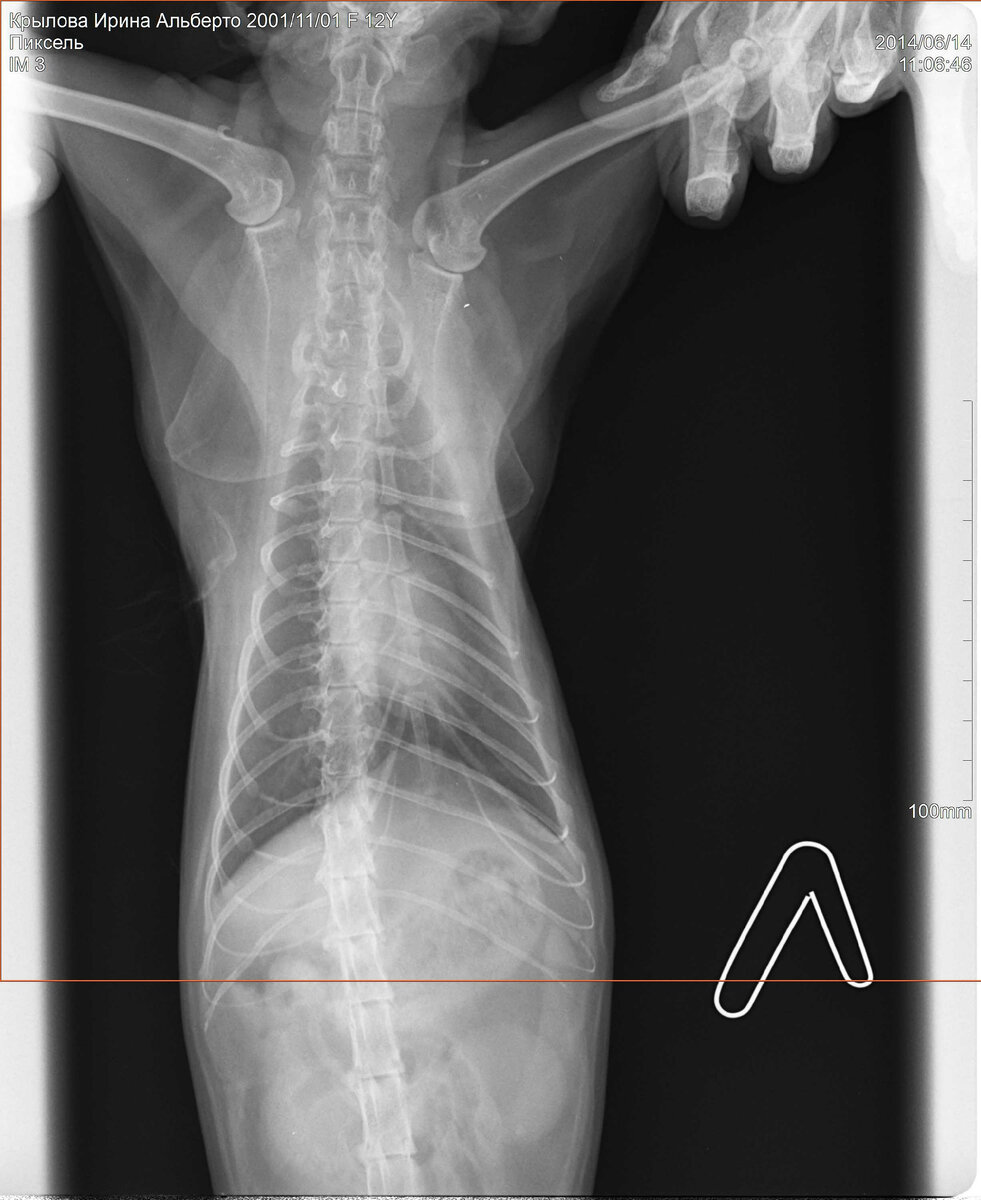

Мы конечно сразу побежали в клинику ближайшую (самую современную на тот момент и самую дорогую в городе). А доктор руками разводит - надо рентген - езжайте в другую клинику. Поехали, сделали - а врач говорит "всё плохо" и шансов нет, езжайте к своему доктору и думайте про "искусственный уход на облачко".

Рентген Пикселя.

В качестве диагноза нам объяснили, что в легких нашей кошки какие-то спайки и "слипшиеся" образования. Что-то вроде "рака легких" по сути...

Не знаю как, почему и что произошло, но спустя 2 недели врачи порекомендовали нам сделать повторный снимок рентгена. И вы знаете, он стал значительно лучше! Те образования, которые видели доктора почти пропали. Конечно, по рекомендации доктора мы продолжили лечение до полного выздоровления.